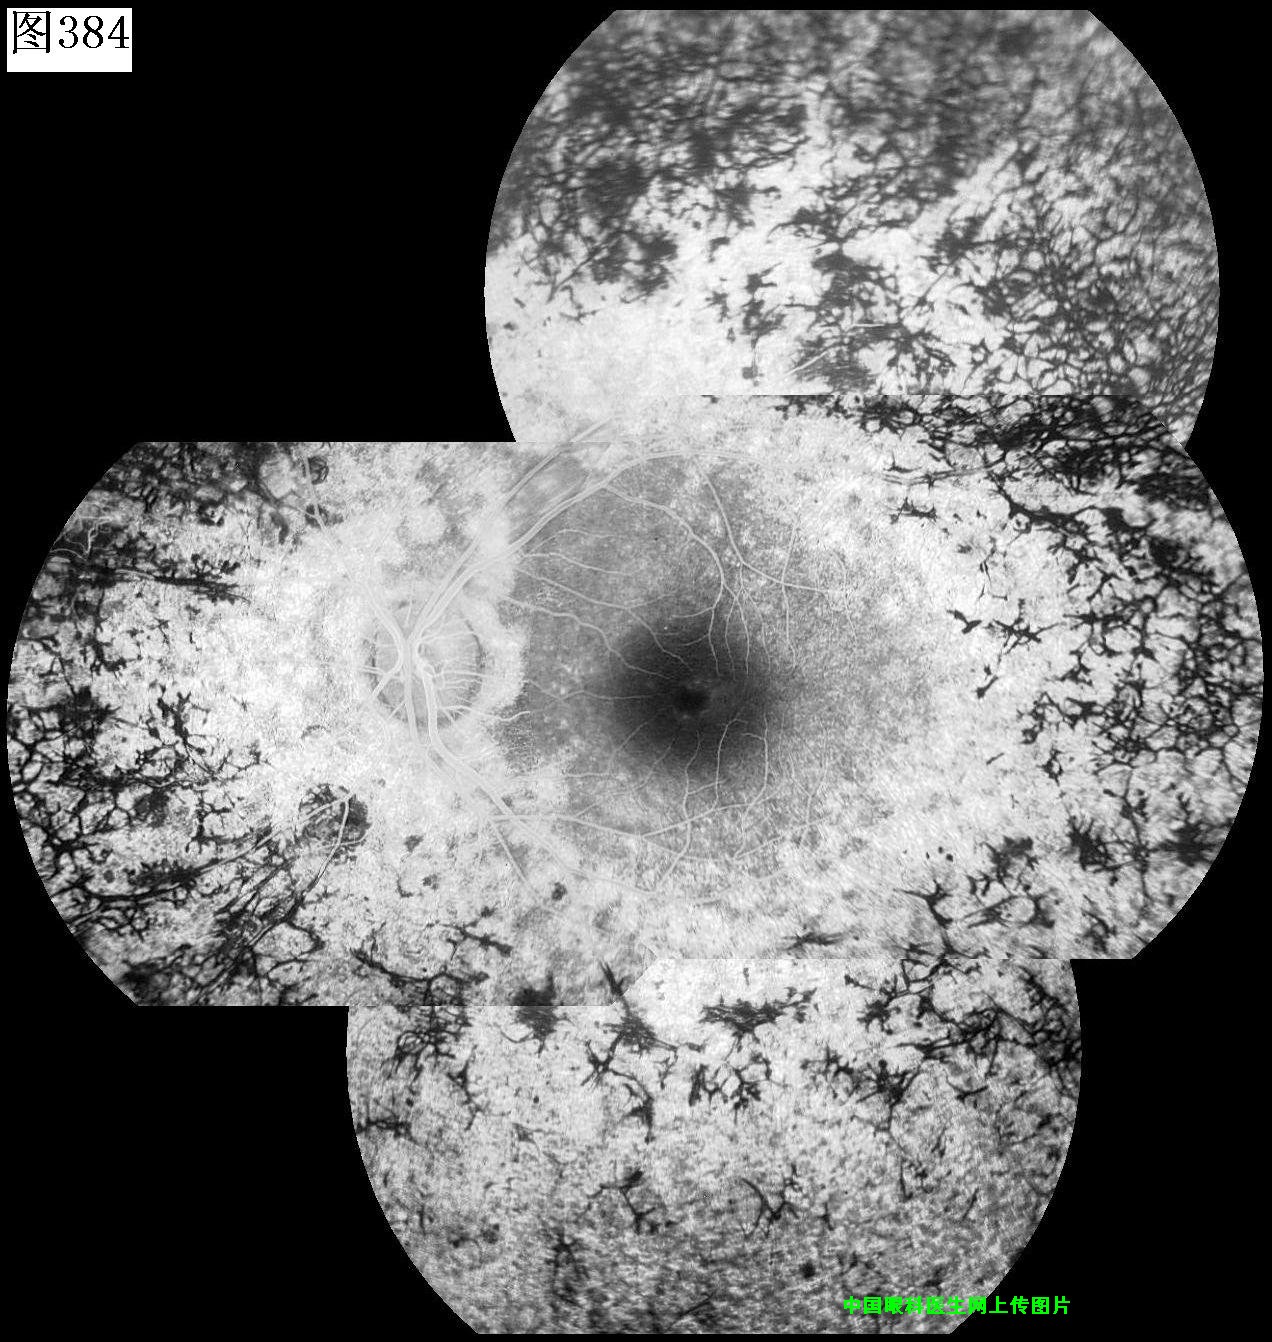

381 382 383 384